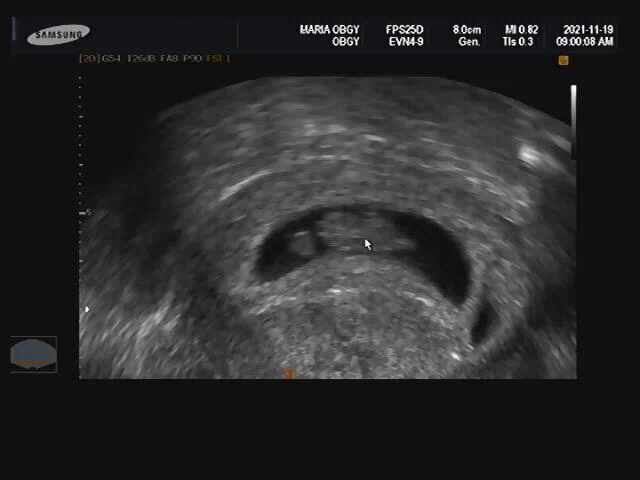

찰떡이 올챙이되다?

세번째 초음파 역시나 후둥이가 예후가 안좋다고 하셨는데.. 역시나 그뒤로 성장이 멈추고 자연 소실되고 ...